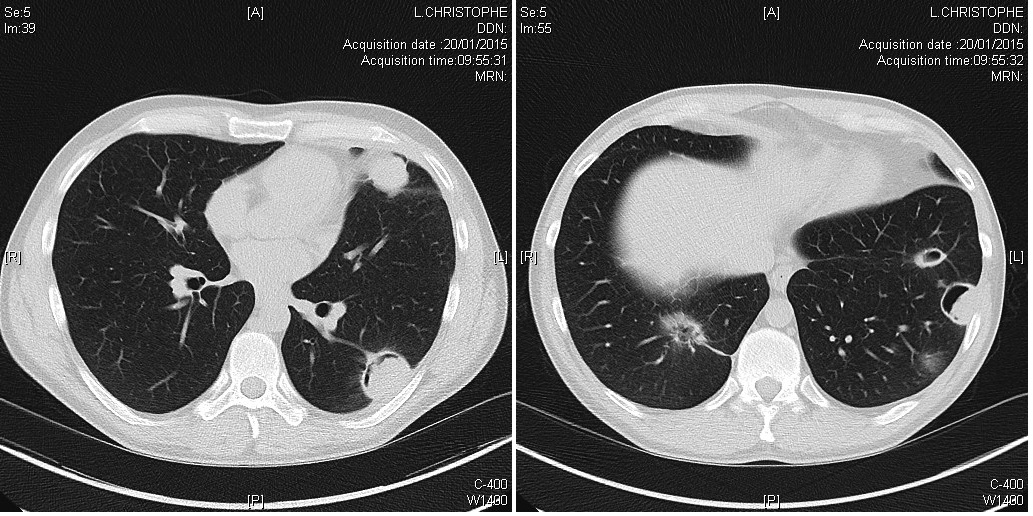

Scanner

Nodules plumonaires excavés dans le cadre d'une granulomatose avec polyangéite